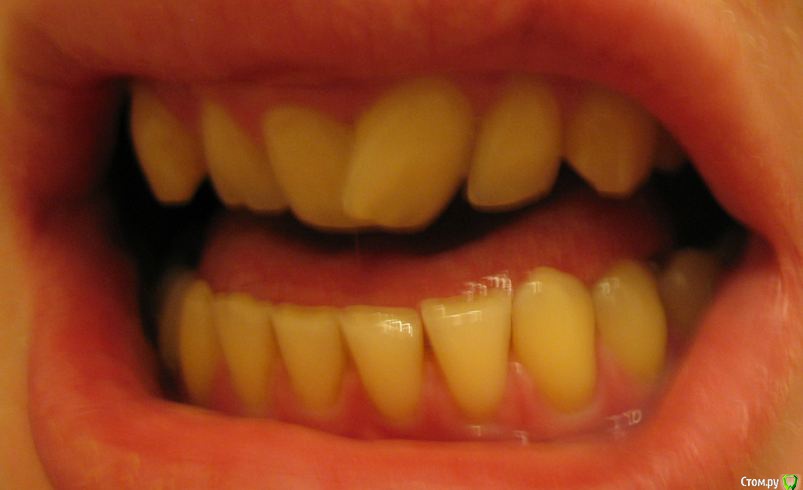

Мне 28 лет. У меня нет ни одной пломбы. Всю жизнь я хожу к стоматологом только на гигиеническую чистку. Последние несколько лет мне уже несколько врачей рекомендовали удалить четвёрки и поставить брекеты для исправления дистального прикуса. Один из ортодонтов также предлагал ЧЛХ нижней челюсти. Основной аргумент у врачей, что если не снизить нагрузку на дёсны от неправильного прикуса, то уже лет через 5 зубы начнут выпадать. Как видно на фото, дёсны уже значительно сползли, появился клиновидный дефект. С эстетической точки зрения меня всё устраивает. Хочу услышать ещё несколько мнений, как бороться с опусканием дёсен и стоит-ли заниматься исправлением прикуса.